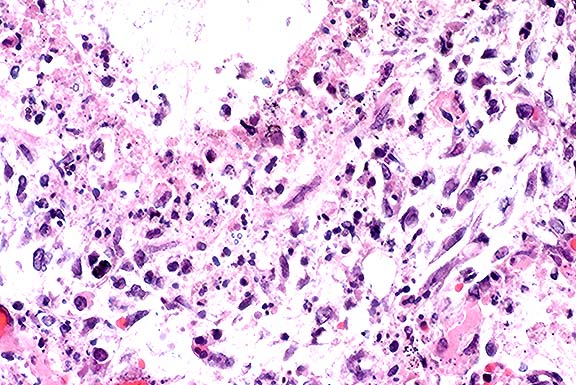

Contributor's Diagnosis and Comments: Enteritis, granulomatous, diffuse, chronic, severe, with diffuse granulomatous lymphadenitis and multifocal lymphogranulomatous phlebitis, lymphangitis and arteritis, mixed breed, adult ovine, caused by acid-fast bacilli, Mycobacterium avium var paratuberculosis, Johne's Disease.

In this case, there is extensive atrophy of normal mucosal

components, which are replaced by an extensive infiltrate of macrophages

into the lamina propria and submucosa, and also with variable

numbers of lymphocytes, plasma cells, neutrophils and eosinophils,

and generally low numbers of Langhans giant cells and epithelioid

macrophages. Peyer's patches are hyperplastic, and mesenteric

attachments are edematous. There are nodular areas of vasculitis

and lymphangitis (not present in all sections). Although the surface

epithelium is absent in most areas, this is interpreted as an

artifact associated with autolysis and not an ulcerative process.

The macrophages throughout the intestinal lesions are distended

with mycobacteria, confirmed by Ziehl Nielsen stains, but apparent

as fine basophilic cytoplasmic stippling in H&E-stained sections.

The lesions are typical for the so-called lepromatous or multibacillary

form of ovine Johne's disease (JD). A second form of the disease

in small ruminants, the paucibacillary form, has few organisms,

few infected macrophages and the inflammatory lesions are predominantly

lymphocytic rather than granulomatous. In this second form, the

diagnosis may be difficult to confirm, either by histopathology

or by culture.